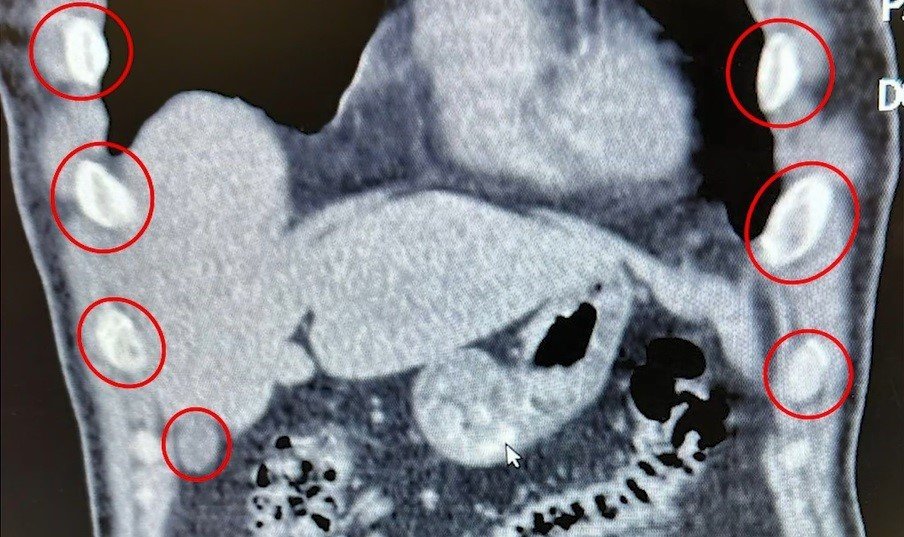

Bitlis’te düzenlenen narkotik operasyonunda yabancı uyruklu iki şüpheli, midelerinde taşıdıkları 136 uyuşturucu kapsülleriyle yakalandı.

Bitlis İl Emniyet Müdürlüğü Narkotik Suçlarla Mücadele Şube Müdürlüğü ekipleri, uyuşturucu ile mücadele kapsamında önemli bir operasyona imza attı. Tatvan ilçesinde durdurulan bir otobüste yolcu olarak seyahat eden yabancı uyruklu 2 kişi gözaltına alındı. Şahısların yapılan tıbbi müdahalesinde, yuttukları 136 kapsül halinde toplam 1 kilo 48 gram metamfetamin ele geçirildi.

Midelerinden 136 kapsül uyuşturucu çıktı